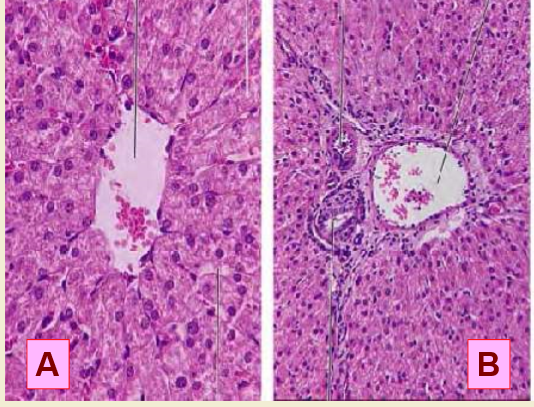

Q

A is a picture of? B is a picture of?

A

A= central vein

B= portal triad